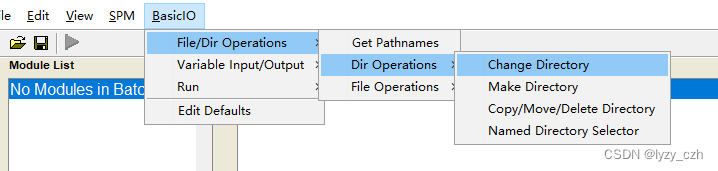

2、转到工作路径